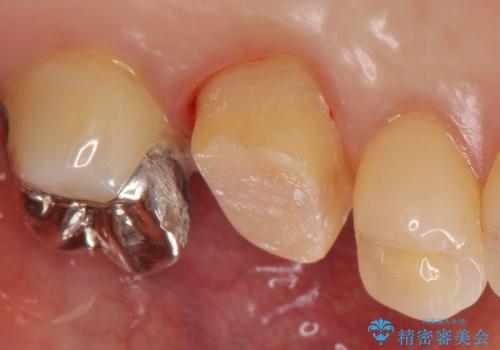

割れた被せ物を作りなおしたい

- 他院で装着した被せ物が割れたとのことで来院されました。

被せ物の厚みが確保されていなかったため、向かいの歯とのスペースを確保するように修正していきます。

被せ物の厚みが十分に確保できていないと、材料によっては今回のように割れてしまうことがあります。

被せ物の材料を変えるか、厚みを確保することでそのリスクを抑えることができます。

今回はセラミックでの再治療をご希望されたため被せ物の厚みを確保することで対応しました。